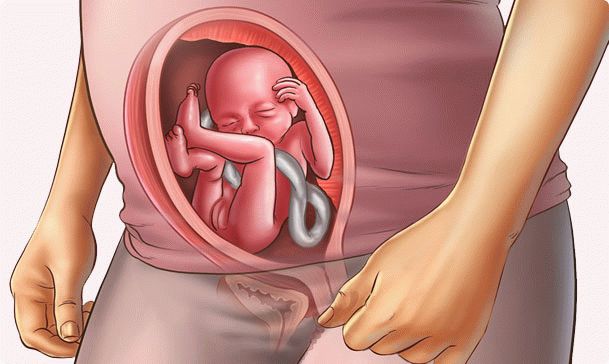

fetus at week 20

Inside you, a real man grows up. It has proportions almost like that of a newborn. Growth is 14-16 cm, and weight is about 260 g. The fetus spends almost all day at rest, and moves only a few hours every day. The tiny brain sends signals, and your baby "tries the forces":

• moves the arms and legs;

• turns with the whole body;

• moves his head;

• opens and closes a mouth;

• sucks fingers (usually "comes across" big);

• sometimes grabs the umbilical cord;

• slightly inflates the chest, as if breathing.